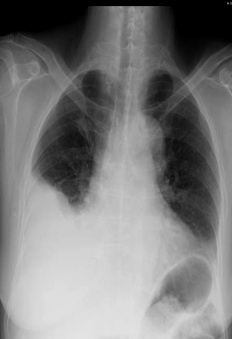

解題:片中可見肋膈角消失,根據公式得出胸腔積液